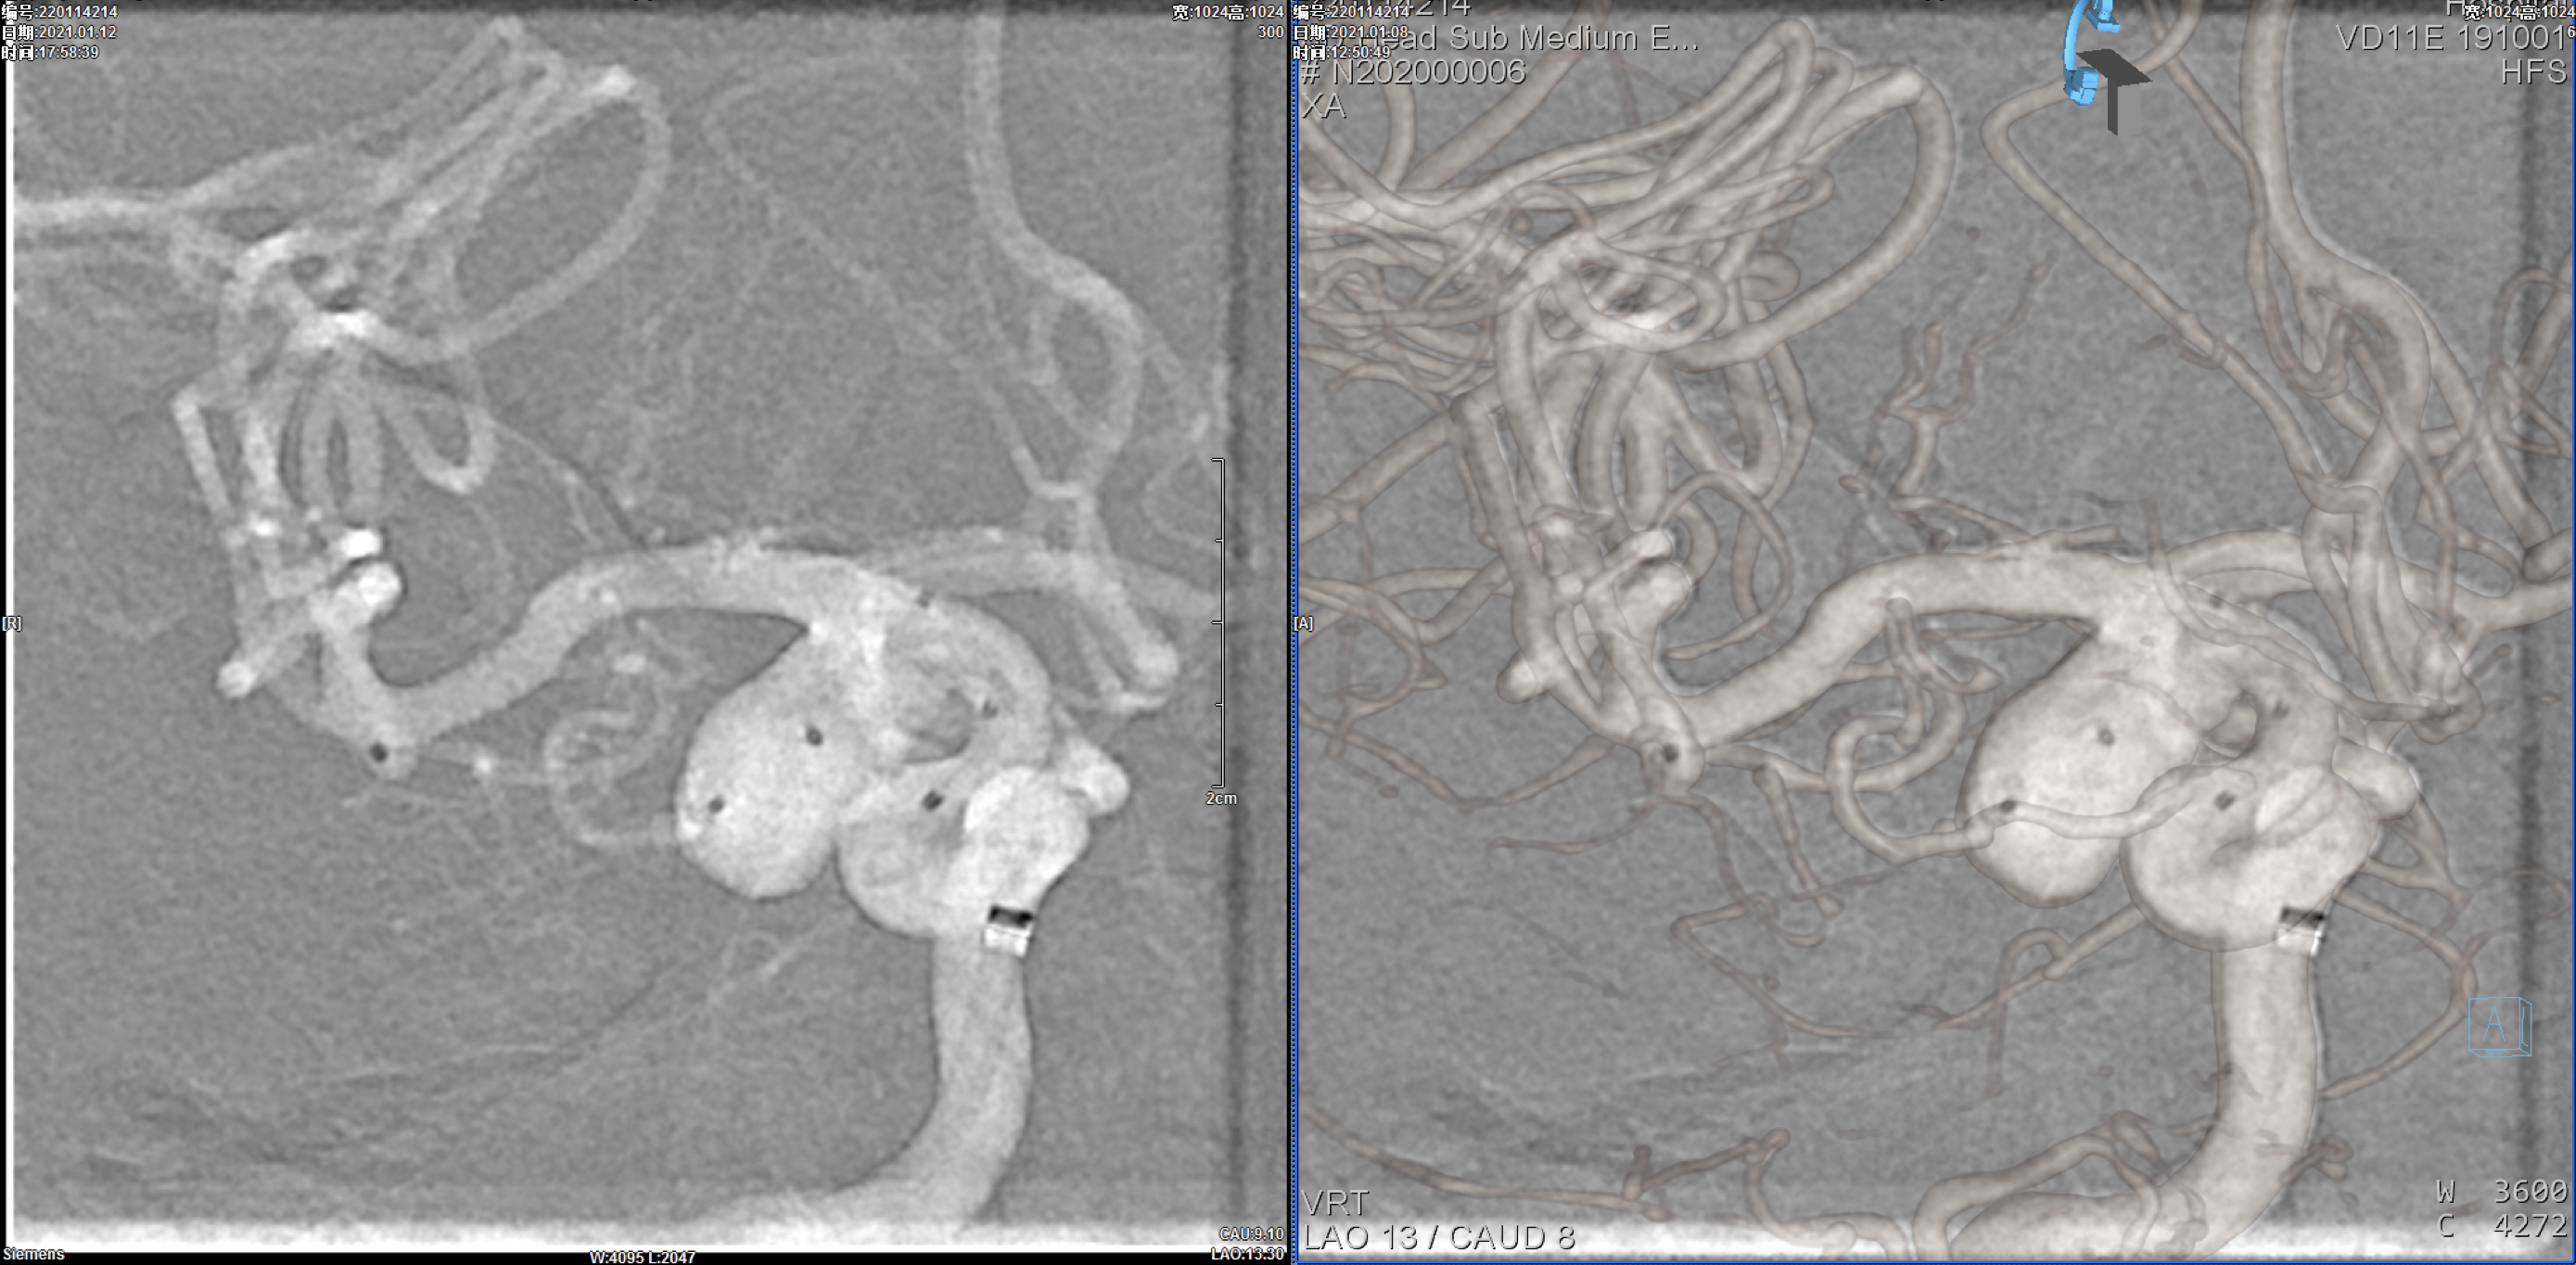

右颈内动脉三维重建:粗大的后交通动脉自近心端瘤颈发出!闭塞后交通动脉可能会出现临床症状,似乎可以通过支架的推“灯笼”保护,但瘤体较大,尽可能栓塞完全,故考虑瘤腔内双微导管分区填塞!

通过7F长鞘+6F Navien同轴输送至颈内动脉岩段

选择Lvis3.5mm*20mm支架半释放保护下经瘤腔深部栓塞微导管送入第一枚16mm*52cm弹簧圈后,经另一根栓塞微导管交替分区填塞动脉瘤瘤体!

完全释放支架后,处理瘤颈部!共送入9枚栓塞弹簧圈!